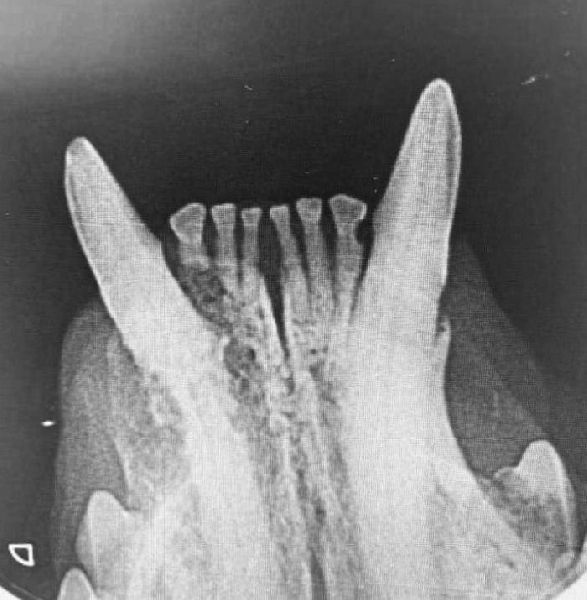

Wir sind eine modern ausgestattete Tierarztpraxis mit großem Leistungsspektrum. Unsere Praxisphilosophie ist Ihr Anspruch auf eine bestmögliche Versorgung ihres Tieres mit neuestem Wissen, herzlicher Fürsorge und entgegenkommendem Service. Wir tun für Ihr Tier genau das, was wir bei unseren eigenen Tieren auch machen würden - unsere Haustiere sind zu Mitgliedern der Familie geworden! Wir möchten Ihnen und Ihrem Liebling von Anfang an beratend zur Seite stehen. Die Tierarztpraxis bietet Vorsorgeuntersuchungen für jeden Lebensabschnitt Ihres Tieres an. Für die Diagnose von akuten und chronischen Beschwerden stehen uns ein Sofortlabor (für die sofortige Auswertung von Blut,-Urin,- und Kotproben), ein modernes digitales Röntgengerät mit geringer Strahlenbelastung sowie ein mod. Ultraschallgerät zur Verfügung. Ein Schwerpunkt unserer Praxis ist die Behandlung von Hunden, Katzen, kleinen Heimtieren (Kaninchen, Meerschweinchen und Hamster), insbesondere die Durchführung von Zahnbehandlungen.

#2 Behandlungsräume #Barfberatung #Chirurgie #Dentalröntgen #Digitales Röntgen #Ernährungsberatung #Heimtiere #Inhalationsnarkose #Krankenstation #Modernes Ultraschallgerät #Moosach #Narkosemonitoring #Online Terminvereinbarung #Rationsberechnung für Hund und Katze #Schwerpunkt Zahnheilkunde #Sofortlabor Blut/Kot/Urin #Tierarzt #Zahnmedizin inkl. Zahnröntgen